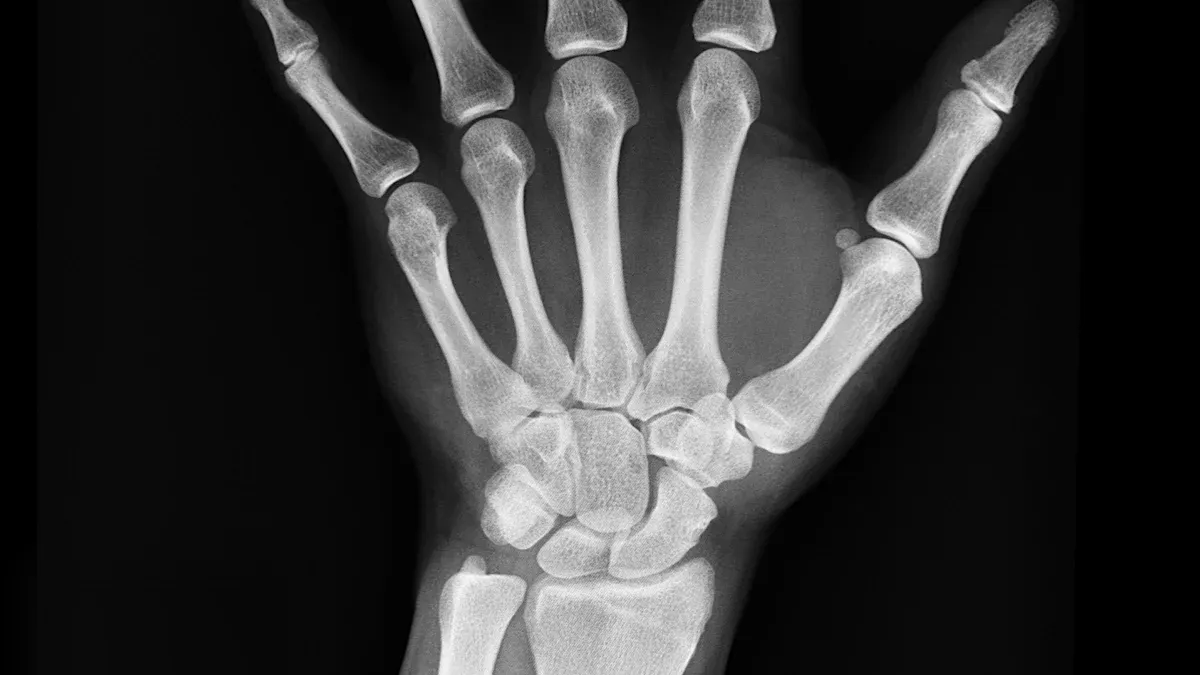

When selecting an X-ray detector backplane for your X-ray system, it’s important to consider how its features will impact your imaging results. The X-ray detector backplane serves as the foundation of your X-ray system, converting X-rays into digital images for analysis or diagnosis. Matching the technical specifications of the X-ray detector backplane to your specific requirements is essential. For instance, in a medical X-ray system, high resolution ensures clear and detailed images, a low dose enhances patient safety, and fast imaging speed allows for quick image acquisition. The table below highlights how these features influence your decision:

When you pick a dr panel, you want clear images. Good image quality is very important for your work. You should check for high contrast, the right density, and sharp resolution. These things help you see small parts and tiny changes in tissues or materials. If your images are clear, you can make better choices when you check or diagnose something.

Radiation dose and sensitivity are very important when you choose a dr detector. You want to use the lowest dose you can, especially in medical imaging. Low-dose dr panels help keep patients and workers safe by lowering exposure. High sensitivity means the dr panel can still make clear images, even with less radiation.

Modern dr panels, like BOE’s, use new materials and digital design to be more sensitive. These panels can make good images with less radiation than old systems. This means you get safety and good performance. In hospitals, low-dose dr panels help lower risk and keep image quality high.